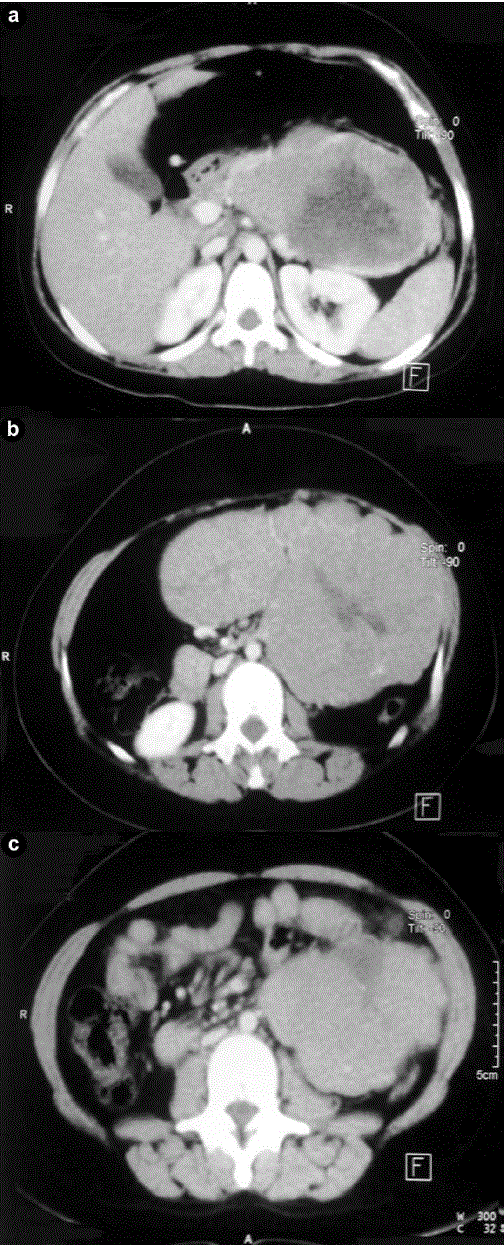

Figure 1. Abdominal CT scan shows a large, well-demarcated, heterogeneous pancreatic mass